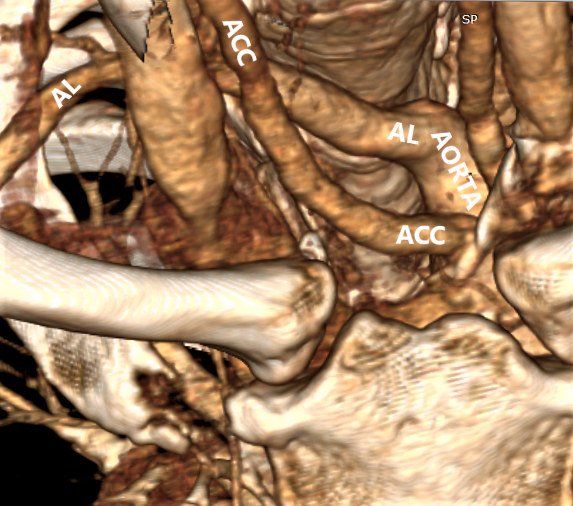

Рис. 2. Пациентка 32 лет, индекс массы тела (ИМТ) – 18,5. а – УЗИ сосудов верхнего средостения конвексным датчиком в В-режиме (цветное дуплексное сканирование менее информативно из-за множества помех от дуги аорты). Правая общая сонная артерия прослежена до дуги аорты (БЦС не выявлен). б – интраоперационная картина. НВГН IIA типа (по Avisse–Toniato) имеет горизонтальный ход. в – аксиальный КТ-скан с ангиографией сосудов дуги аорты. AL располагается позади трахеи и пищевода. г – компьютерная трехмерная реконструкция демонстрирует синтопию AL с общей сонной артерией. AL является последней, четвертой ветвью дуги аорты. ACC – arteria carotis communis dexter, TR – trachea, E – esophagus.

Рис. 3. Пациентка 58 лет, ИМТ – 21,7. а – цветное дуплексное сканирование сосудистого пучка правой половины шеи линейным датчиком на уровне правого грудино-ключичного сочленения. Правая общая сонная артерия прослежена до места “пересечения” с трахеей (БЦС не выявлен). AL располагается на значительном расстоянии от правой общей сонной артерии. б – интраоперационная картина. НВГН I типа (по Avisse–Toniato) имеет нисходящее направление и состоит из двух веток (стрелки). в – аксиальный КТ-скан с ангиографией сосудов дуги аорты. AL располагается позади трахеи и пищевода. г – компьютерная трехмерная реконструкция демонстрирует синтопию AL с общей сонной артерией. AL является последней, четвертой ветвью дуги аорты. ACC – arteria carotis communis dexter, TR – trachea, E – esophagus. VJI – vena jugularis interna dexter, NV – nervus vagus dexter.

Рис. 4. Пациентка 68 лет, ИМТ – 31,6. а – УЗИ сосудистого пучка правой половины шеи линейным датчиком в В-режиме. б – цветное дуплексное сканирование сосудистого пучка правой половины шеи линейным датчиком. AL расположена параллельно плоскости сканирования. Правая общая сонная артерия и трахея находятся перпендикулярно относительно датчика. в – интраоперационная картина. Мобилизована правая доля ЩЖ, отведена медиально. НВГН состоит из двух веток (стрелки). г – интраоперационная картина. Выполнена тиреоидэктомия. НВГН IIA типа (по Avisse–Toniato) имеет горизонтальный ход. д – аксиальный КТ-скан с ангиографией сосудов дуги аорты. AL располагается позади трахеи и пищевода. е – компьютерная трехмерная реконструкция демонстрирует синтопию AL с общей сонной артерией. AL является последней, четвертой ветвью дуги аорты. ACC – arteria carotis communis dexter, TR – trachea, E – esophagus.

Рис. 5. Пациентка 62 лет, ИМТ – 51,4. а – УЗИ сосудистого пучка правой половины шеи конвексным датчиком. AL “выходит” из-за трахеи и расположена практически горизонтально, высоко на границе шеи и верхнего средостения. б – интраоперационная картина. НВГН IIA типа (по Avisse–Toniato) имеет горизонтальный ход. в – аксиальный КТ-скан с ангиографией сосудов дуги аорты. AL располагается позади трахеи и пищевода. г – компьютерная трехмерная реконструкция (вид сзади). AL является последней, четвертой ветвью дуги аорты. ACC – arteria carotis communis (А – dexter, D – sinister), TR – trachea, E – esophagus. VJI – vena jugularis interna dexter, AS – arteria subclavia sinister.

Всем 4 пациентам с выявленными AL и НВГН в послеоперационном периоде выполнена мультиспиральная КТ-ангиография. AL во всех случаях располагалась за пищеводом. При ретроспективном опросе только у 2 больных отмечены периодические неприятные ощущения при проглатывании твердой пищи, которые им не приносили неудобства и оставались долгое время незамеченными. До операции всем пациентам проведена эзофагогастродуоденоскопия – стриктур, патологических образований пищевода не отмечено.